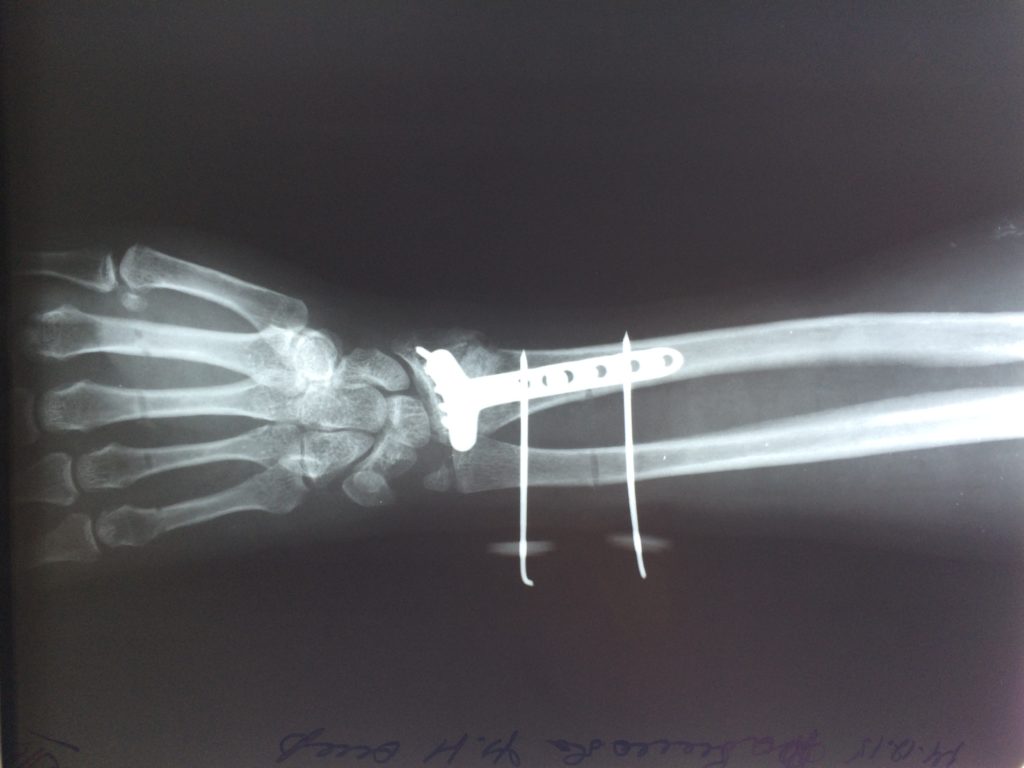

Операция - открытая репозиция, остеосинтез лучевой кости пластиной с костной ксенопластикой материалом "Остеоматрикс". На контрольных снимках в три месяца имеется консолидация перелома, миграции фиксатора нет, имеется остеоинтеграция ксенопластического материала.

Отдаленные результаты через 3 (три) месяца: